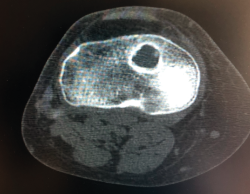

Figura 19. Dilatación del túnel tibial.

Ahora bien, existe un fenómeno de expansión/dilatación de los túneles óseos que perjudica a la correcta fijación de la plastia (Figura 19). Esta dilatación puede incluso conllevar a la aparición de fístulas de líquido sinovial. Esta situación conocida como “efecto parabrisas” ocurre cuando el túnel no se ajusta perfectamente a la plastia y se da mayor frecuencia con el uso de plastias de isquiotibiales, el uso de aloinjertos e implantes sintéticos. Se recomienda usar tornillos interferenciales que bloqueen la plastia lo más cerca posible de su salida a la articulación para evitar este efecto(40).